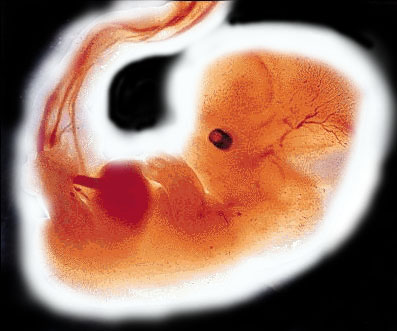

5 - 6 週

莫勒教授的著作裡在中世紀的標題下:『在中世紀,科學發展得很緩慢,人們對於胚胎學所知很少,而在穆斯林那裡,《古蘭經》卻提到人類的孕育與生長。人是由男女兩性的精液、卵細胞結合而受孕,並在多處指出人由受精卵而孕育,同時闡明了受精卵六天後像一粒種子般地植入母腹中。現今科學已證實了受精卵在著床後開始分化並在六天後開始生長。《古蘭經》也提到了受精卵逐漸生長,變成一團血塊。分裂後的受精卵,很像「阿來格」 (血塊)可以看到那個階段胚胎的外貌類似於「蛹」(如左圖所示)。圖中胚胎與「蛹」或水蛭在外形上沒有什麼二樣,在下一階段胚胎的外貌就像被咬過一口的奶酪或木片,如圖所示。胚胎已具有人的跡象。在過了四十一或四十二天後,胚胎已被認為完全是人的形象了,自此和動物的胚胎已不同了。在該階段胚胎已開始具有人的特徵,就像右圖中所示的樣子。